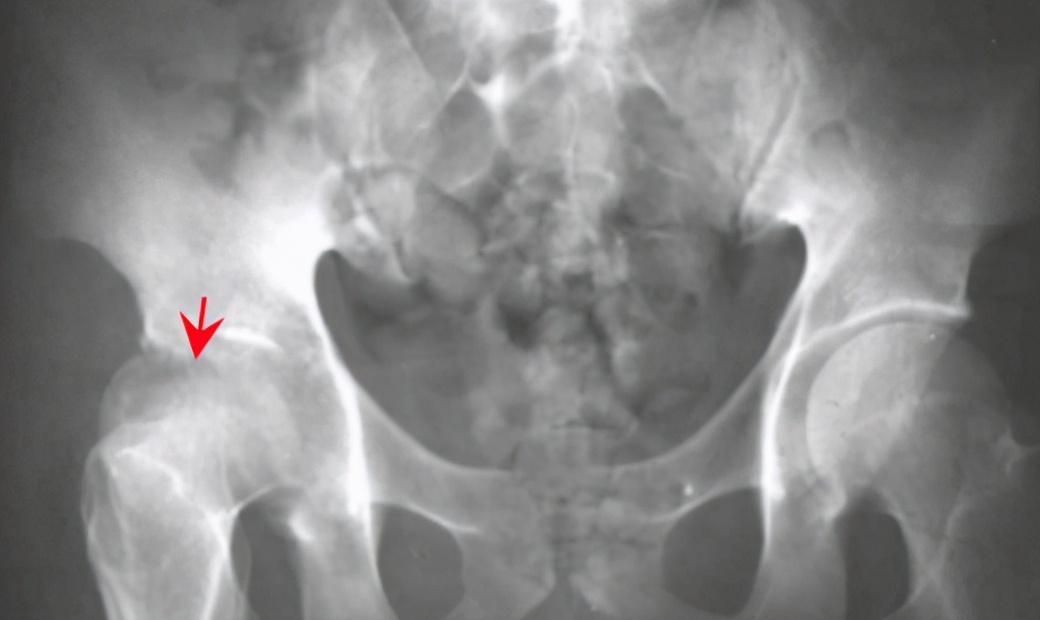

第二种情况的发生是导致化脓性关节炎跟畸形:在骨髓炎没有得到有效及时治疗的情况下,会出现干骺端的化脓性骨髓炎的出现,进而出现脓肿;后者出现的情况是由于骨骺受炎症的刺激,患肢过度生长而变长,或是因为骨骺板受到破坏,因而影响发育,使肢体缩短,骨骺板单侧受到破坏,发育不对称,或是由于软组织疤痕挛缩,而引起畸形。这两种情况都是由于炎症的出现,最有效的方式就是尽早解决炎症的继续扩散,只是要避免使用西药治疗,尽快用中药外敷的形式进行治愈。